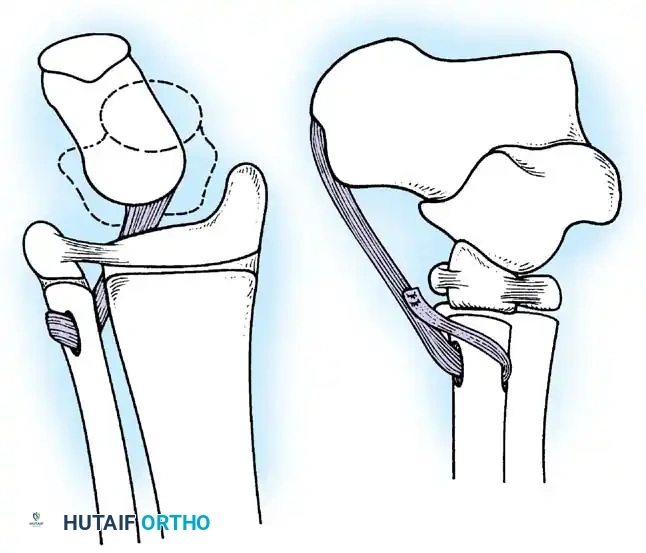

Tendon Transfers for Quadriceps Paralysis:

If the hamstrings are strong (Grade 4 or 5), the biceps femoris and semitendinosus can be transferred anteriorly to the patella or tibial tubercle.

Image

The tendons are mobilized, routed subcutaneously, and woven into the quadriceps tendon or fixed directly to the patella. Postoperatively, the knee is immobilized in extension for 6 weeks, followed by aggressive rehabilitation to achieve phasic conversion of the hamstrings from flexors to extensors.